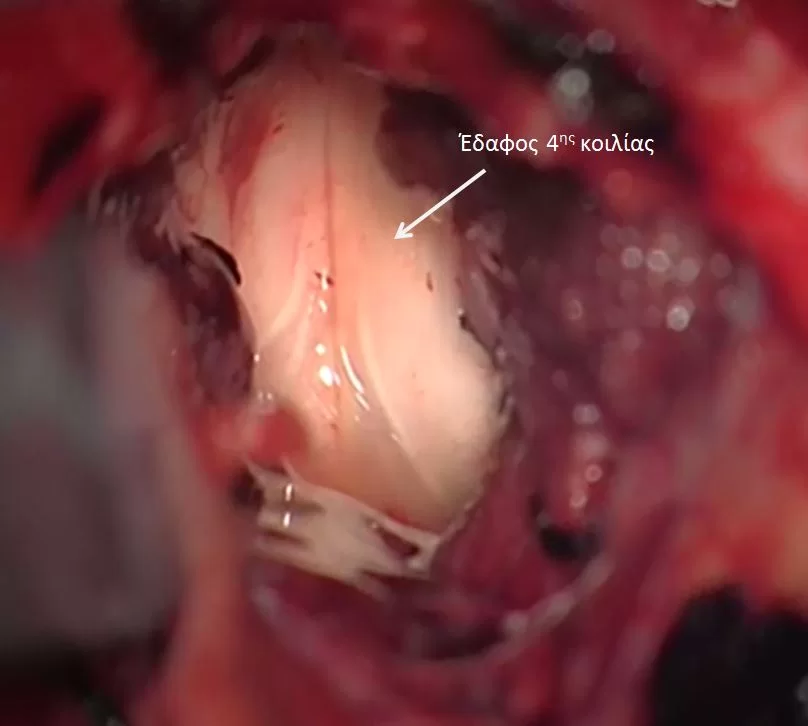

Η μέγιστη ασφαλής αφαίρεση συνιστάται σε όλους τους ασθενείς με ενδοκρανιακό επενδύμωμα. Η ολική εκτομή είναι ο στόχος αλλά δεν είναι πάντοτε εφικτή λόγω της εμπλοκής του στελέχους ή της εγγύτητας με άλλες κρίσιμες δομές.